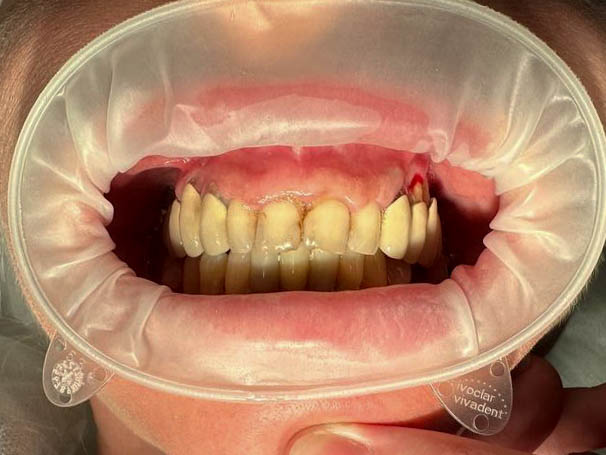

Ситуация до лечения

Пациент обратился с жалобами на эстетические недостатки.

пациент до имплантации